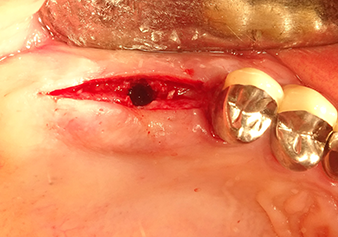

Затем, с помощью инструмента I2A (диаметр 2,0 мм), дно пазухи перфорировалось периодически и в минимально возможном диапазоне. Этот специфический пьезохирургический метод гарантирует, что мембрана Шнейдера не будет повреждена. При использовании Z25P, мембрана уже была слегка приподнята охлаждающей жидкостью, подаваемой через наконечник инструмента (рис. 3). Во избежание высокого давления в ложе имплантата, количество охлаждающей жидкости составляло не более 50%.

Рис.3: После маркировки положения имплантата и первоначального расширения ложа, мембрана Шнейдера деликатно отделяется с помощью инструмента Z25P (фаза 1).